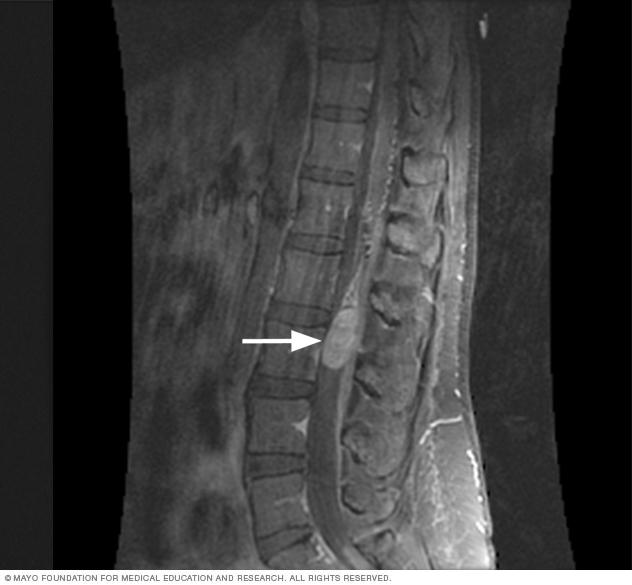

Magnetic resonance imaging, also called MRI, is often used to detect a spinal cord tumor. The white arrow in this MRI scan image points to a spinal cord tumor.

To diagnose a spinal cord tumor, a healthcare professional might start by asking about your symptoms. The health professional might do an exam to see how your nerves are working. Other tests that can help diagnose a spinal cord tumor are imaging tests and biopsy.

Spinal magnetic resonance imaging

Magnetic resonance imaging uses a powerful magnetic field and radio waves to make pictures of the inside of the body. This test also is called an MRI. A spinal MRI can make detailed pictures of your spinal cord. MRI is usually the preferred test to detect spinal cord tumors.

A member of your healthcare team might put a dye into a vein in your hand or arm during the MRI. This dye, called a contrast agent, helps make clearer pictures.